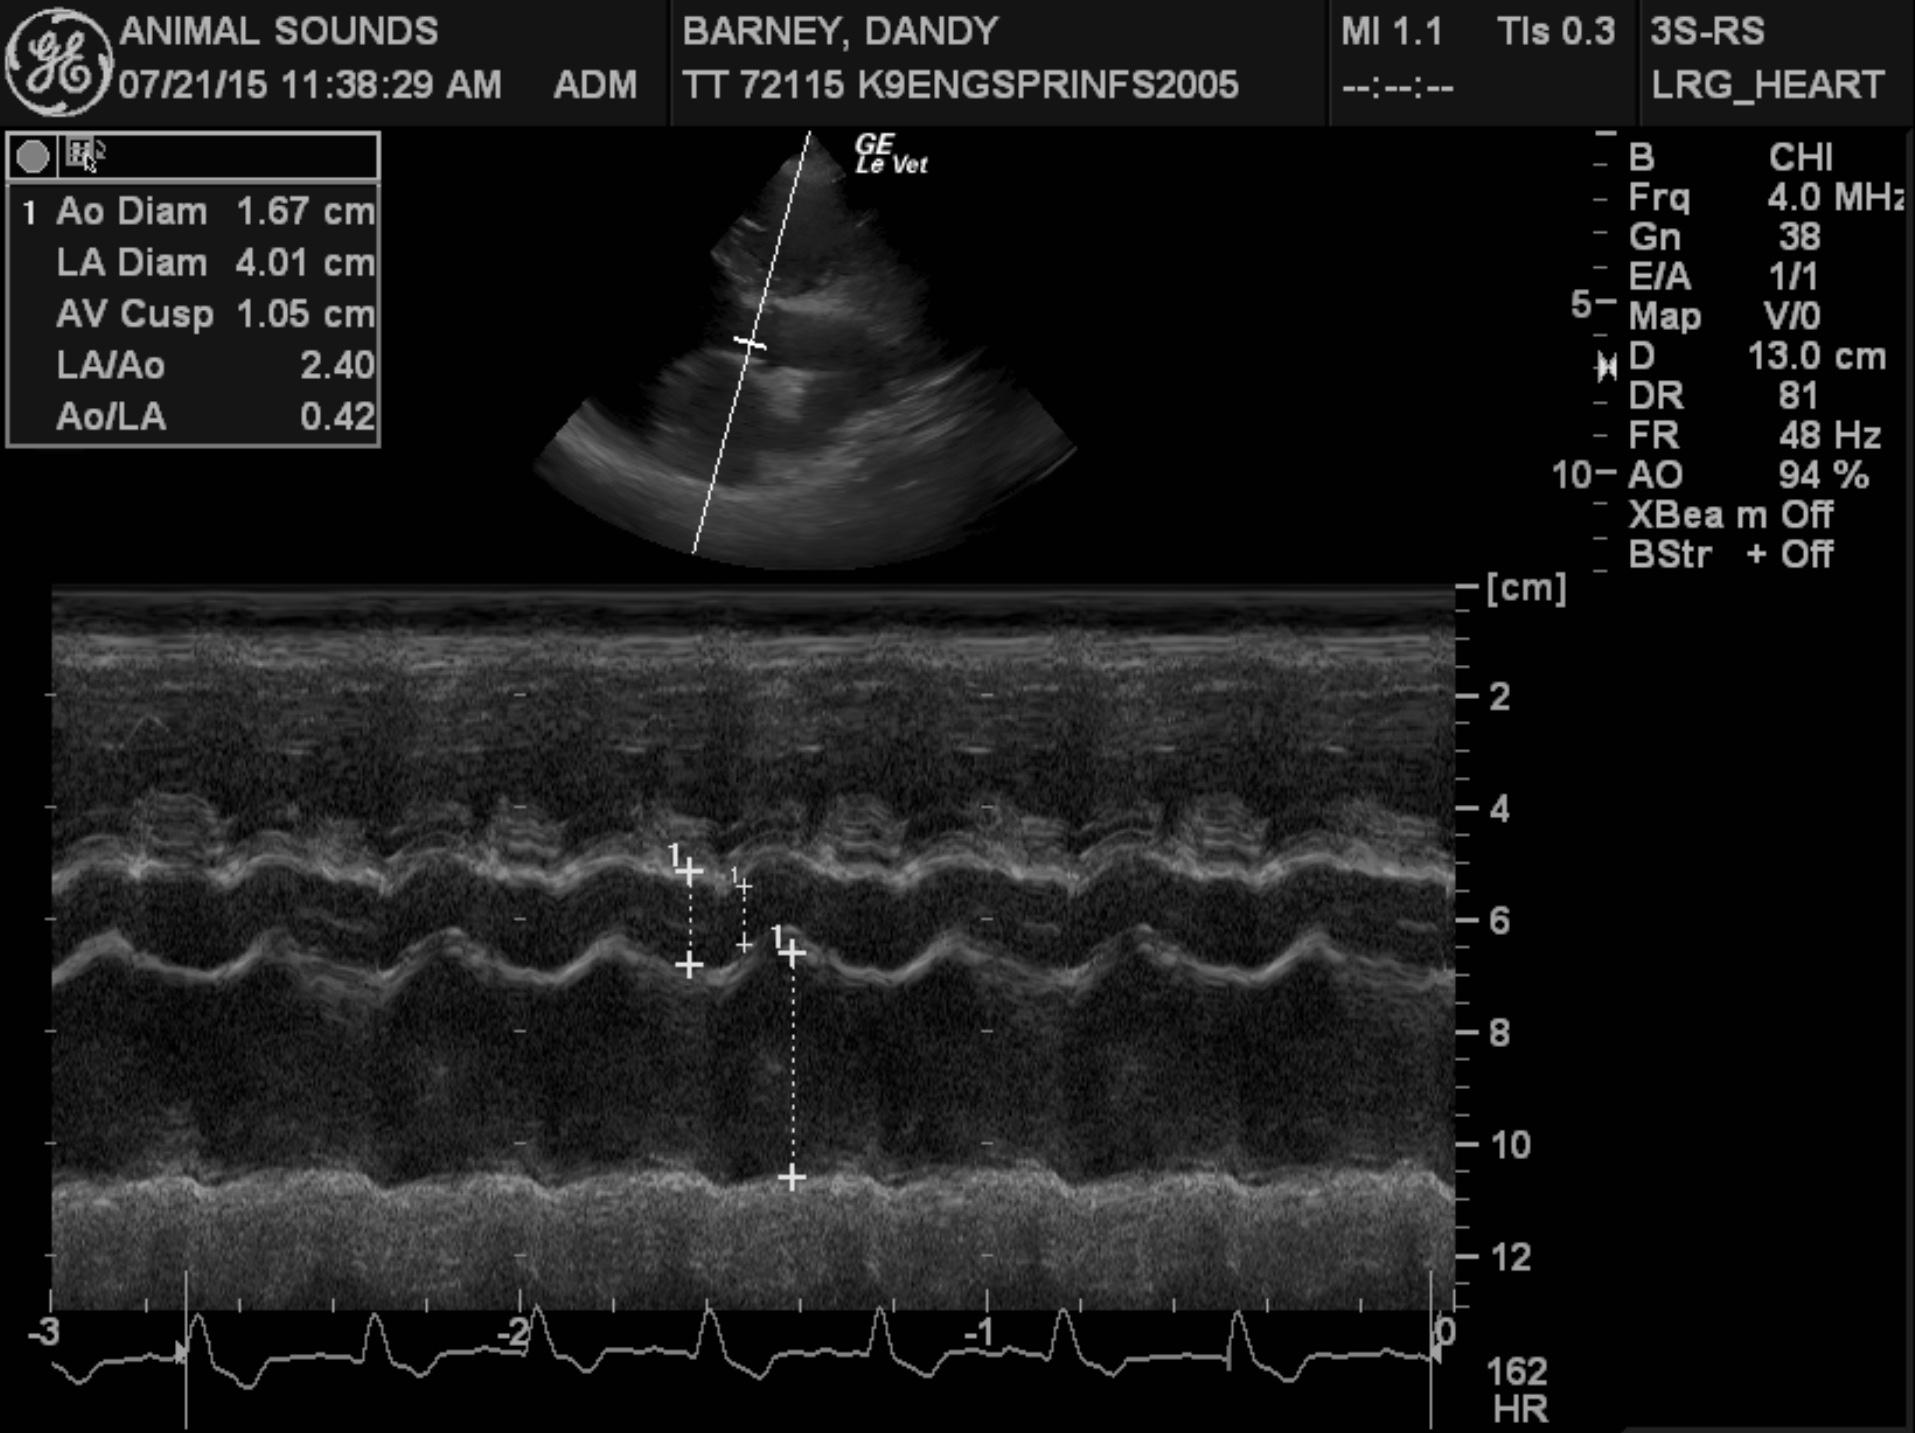

Echocardiogram findings: There is moderate to severe left ventricular dilation. The mitral valve appears normal, though a mild jet of central mitral regurgitation is present. Left ventricular systolic function is globally depressed. The aorta and aortic valve are normal. Right atrial and right ventricular dimensions are normal. The tricuspid valve appears normal, though trace physiologic tricuspid regurgitation is present. The pulmonary artery and pulmonic valve are normal. No pericardial effusion or cardiac masses are seen.

LA – 57.8 mm

LA/Ao – 2.39

This examination demonstrates global left ventricular systolic dysfunction, consistent with dilated cardiomyopathy. Secondary to the patient’s myocardial dysfunction, she has severe left ventricular dilation, as well as moderate to severe left atrial dilation, and it appears that she is in mild congestive heart failure based on her thoracic radiographic findings. Given the severity of her cardiac disease, it appears very likely that this is the cause of her arrhythmia.